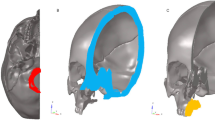

Since this was an in silico study, where all hypotheses were tested digitally, no ethical approval was needed. A finite element model corresponding to half of the skull of an adult human, obtained from a multi-slice computed tomography (Digital Imaging and Communications in Medicine), was generated (Fig. 1) in Renato Archer Technology Information Center (Campinas, Brazil). The model was duplicated with a symmetrical cranium to exactly comprehend the dissipation of forces. This model was created using the software GR model Light-Speed 16 Pro. The elastic properties of the skull (Table 1) were based on previous studies [12, 17].

Three different models of MARME, based on three MARME devices (Fig. 2), were digitally created (Fig. 3). Model A comprised five components: one body screw expander and four adjustable arms with rings for mini-implant insertion. These arms have an individualized height adjustment that allows MARME positioning according to the patient's palatal anatomy (Figs. 2a and 3a), thereby preventing body screw expander collision with the lateral mucosa in severe cases of maxillary deficiency (Fig. 4). Model B was a maxillary expander with screw rings joined to the body (Figs. 2b and 3b). Model C was similar to model B, except that model C had open rings for the insertion of the mini-implants (Figs. 2c and 3c), allowing the orthodontist to angle the mini-implants during their insertion. The distance between the anterior and posterior mini-implants was different in each model. The anteroposterior distance in models A, B, and C was 15 mm, 10 mm, and 9 mm, respectively.

The models were created using computer-aided design (Fig. 4) in the software Rhinoceros (Rhinoceros 5.0 SR11 - Robert McNeel & Associates, Seattle, WA). The same process was used to create the mini-implants [17], which were specific to each MARME appliance tested, although all of them were quite similar. A bicortical insertion of the mini-implants was performed, since it showed better RME results as shown by Lee et al. [18]. The MARME complex was positioned in the distal region of the first upper premolar and distal to the first upper permanent molar [13].